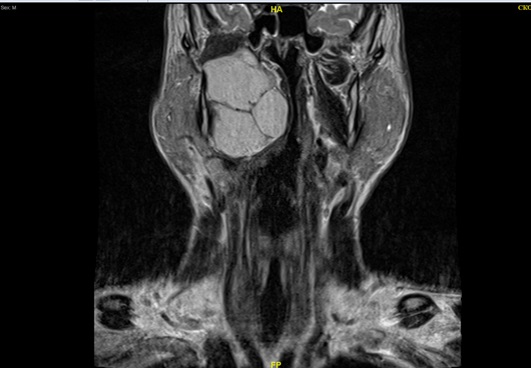

По данным МРТ от 05.02.2023: В правом парафарингеальном пространстве отмечается крупное кистозно-солидное образование с чётким неровным контуром неправильной формы размером 68х75х48 мм. Латерально образование распространяется в сторону околоушного и каротидного пространства, вызывая компрессию проходящих там структур. После проведения МРТ исследования и УЗИ шеи выставлен диагноз «Боковая киста шеи».